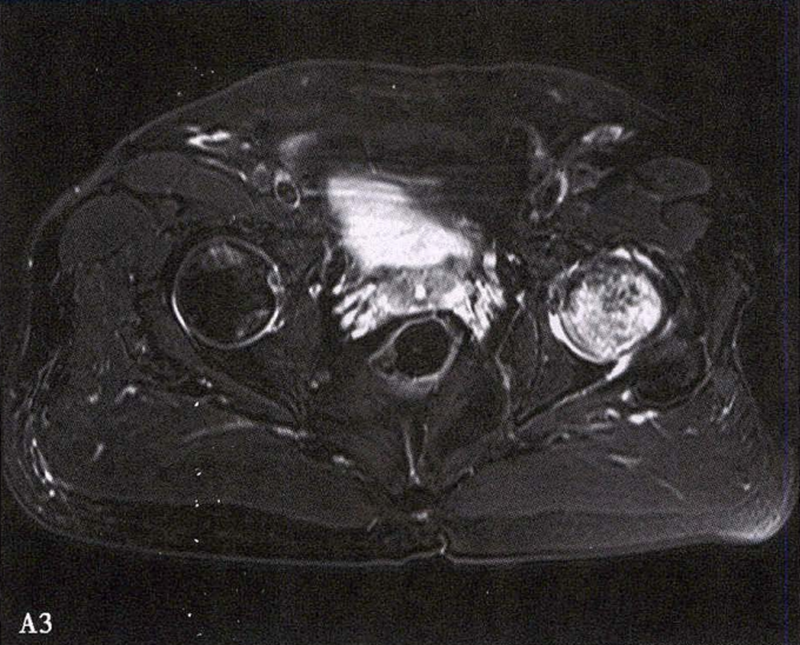

A.男性,71岁,双侧股骨头坏死,右侧Ⅰ期、左侧Ⅲ期。X线片示双侧股骨头形态可,右股骨头未见明显密度改变,左股骨头关节面下见局限性骨密度减低及增高区(A1)。MRI(T2加权像)示右股骨头内双线征,左侧不规则形混杂信号,坏死区远端骨髓水肿(A2、A3)。

B.男性,31岁,双侧股骨头坏死,双侧均为Ⅲ期。X线片示双侧股骨头密度不均、股骨头稍变扁(B1)。MRI(T1加权像)示股骨头内多发不规则信号带(B2),股骨头内凸向大转子的双线征(白色箭)和软骨下骨骨折(白色三角)。